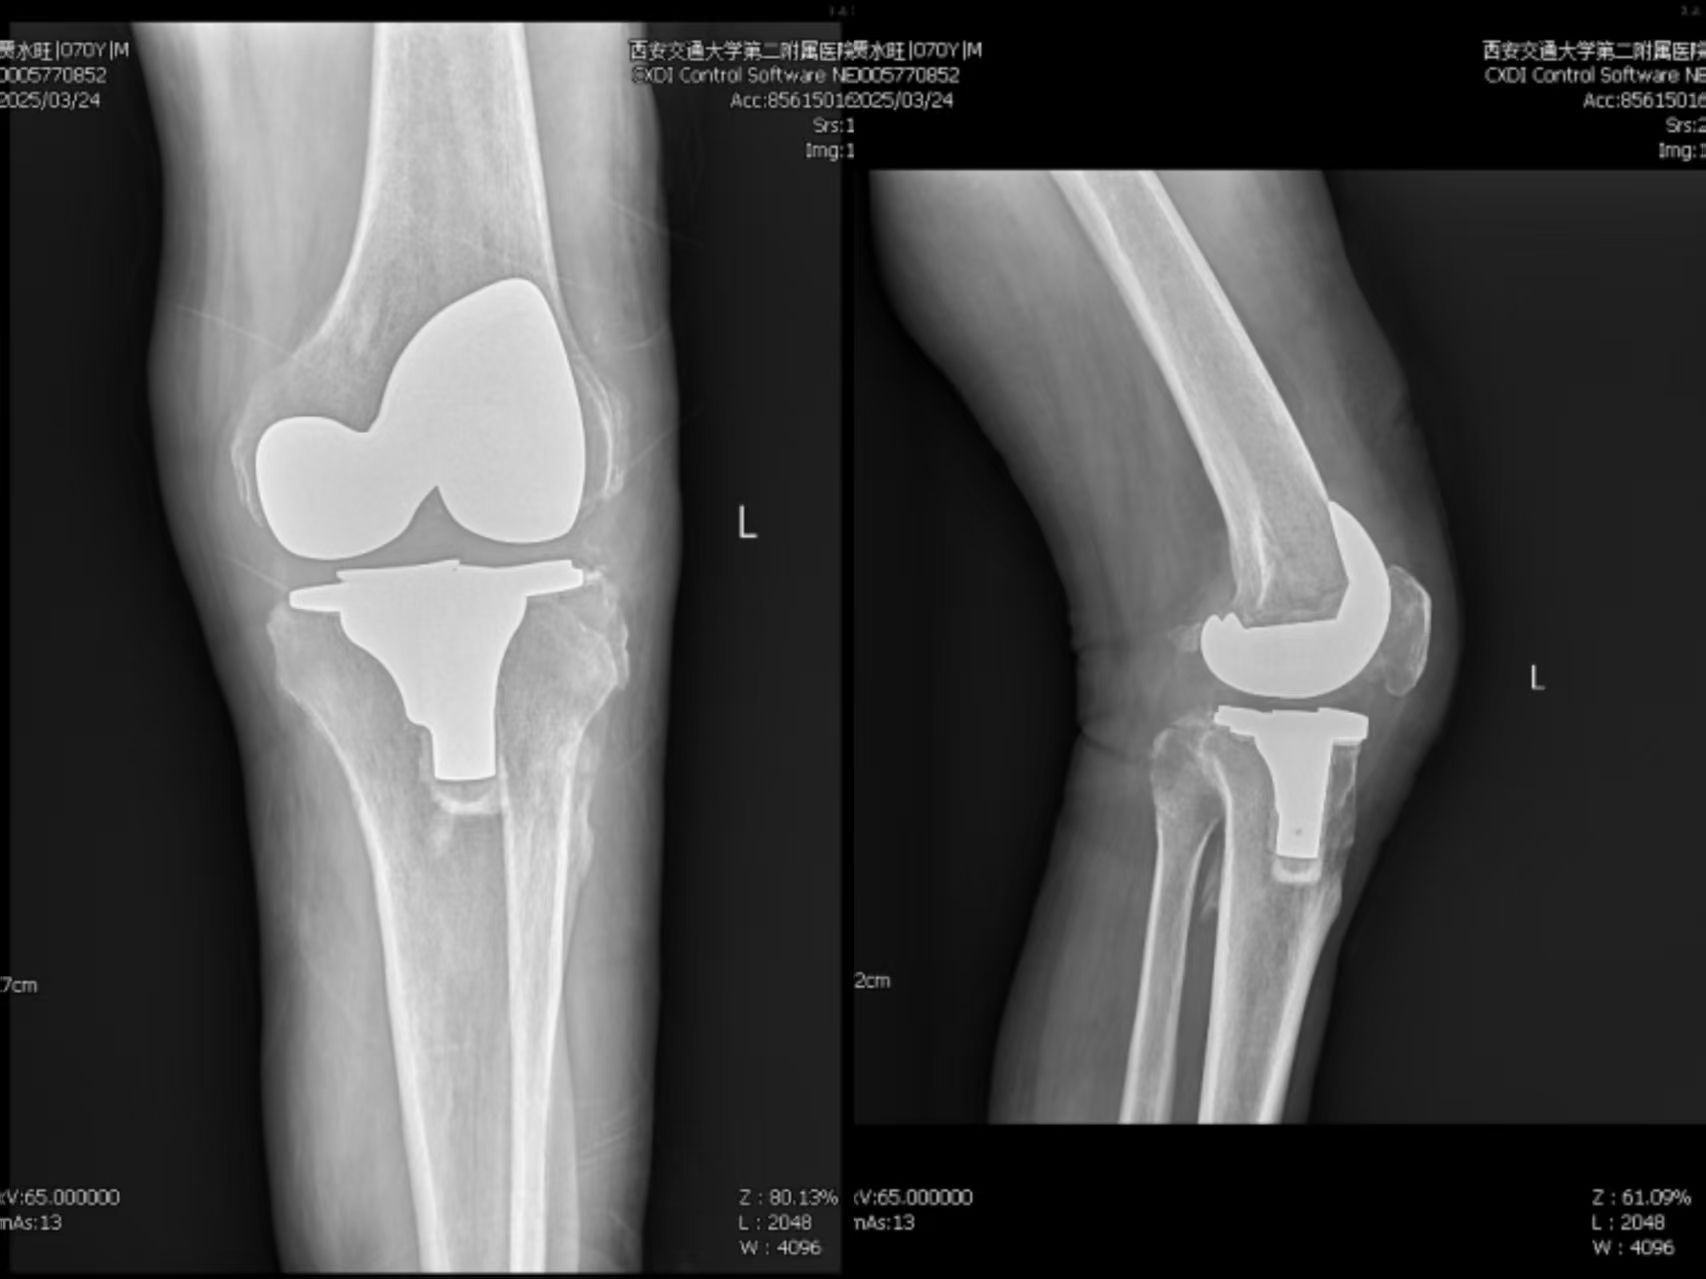

术后患者左膝关节X线正侧位片

术后的第三天清晨,贾伯扶着助行器,在病房走廊留下二十年来第一个完整的脚印。当他转身望向我们时,浑浊的眼底泛起泪光,却比任何术后影像更让我震撼——那是一个医者能见证的最美风景。

术后随访,贾伯不仅关节功能恢复良好,更重要的是未发生任何感染并发症。这个案例的成功,标志着我院在高风险关节置换术的围术期管理质量获得显著提升。未来,我们将持续探索新技术、新方法,助力更多患者重获健康。